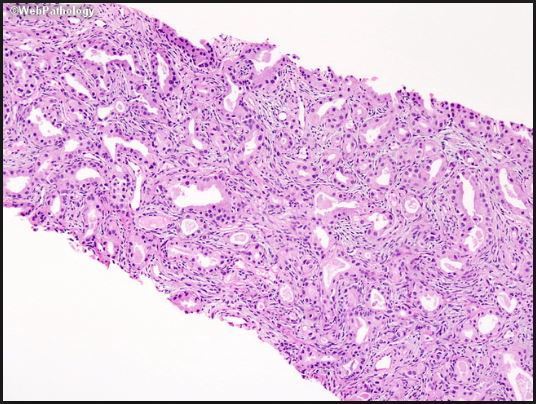

16

Q

Prostate:

adenosis or basal cell hyperplasia?

A

Adenosis

Here is BCH